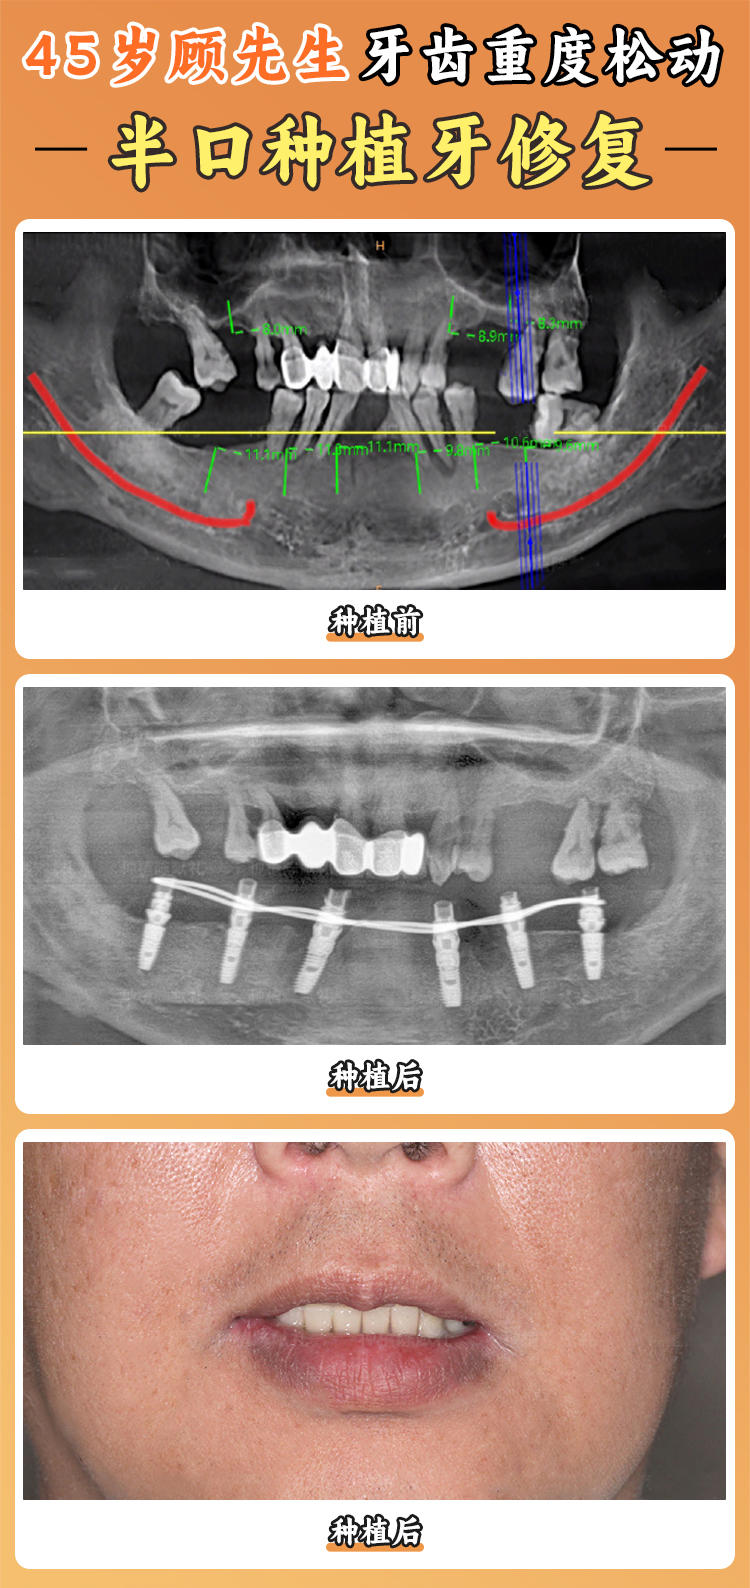

鄭州美奧口腔有一支專精的醫(yī)生團隊。醫(yī)生們平均擁有 8 年以上臨床經(jīng)驗,就像老司機開車,經(jīng)驗多,技術(shù)嫻熟。他們擅長半口牙缺失的即刻修復,對于各種種植牙手術(shù)都特別在行。

比如在面對復雜的種植牙情況時,他們能根據(jù)患者的具體情況,制定出合適的方案。就像裁縫做衣服,量體裁衣,讓患者得到更適合自己的治療。

在價格方面,鄭州美奧口腔也比較合理。單顆韓國登騰種植牙價格為 5000 - 7000 元,半口即刻負重種植價格為 40000 - 60000 元,針對年輕用戶還推出隱形種植美學修復方案,價格為 15000 - 20000 元/顆。

從實例反饋來看,有牙友在美奧口腔種牙后成效良好。比如牙友 A,牙齒缺了 4 顆,在別的醫(yī)院被告知牙槽骨不好,種牙特別貴。但在美奧口腔,醫(yī)生給做了兩套方案,末尾選擇好一點的植體也比之前問的那家便宜不少,種完一年半啥事都沒有,吃飯香得特別。還有牙友 B 的爺爺,做了全口種植牙,術(shù)后當天就能正常吃飯,非常滿意。